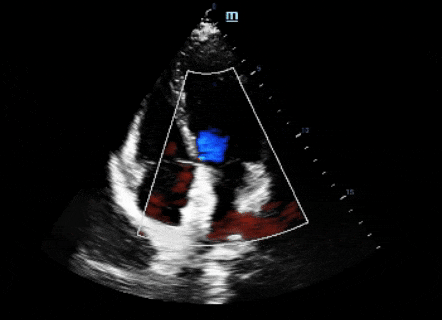

右心聲學(xué)造影:發(fā)泡試驗陽性,心內(nèi)水平巨量右向左分流。

食道超聲(TEE)檢查:提示卵圓孔未閉,房間隔向右房側(cè)稍膨出,基底部寬約18mm,高度約6mm,卵圓窩開口約2.2mm,隧道長度10mm。CDFI:房水平可見少量過隔分流信號。三尖瓣輕度關(guān)閉不全。

常規(guī)股靜脈穿刺,DSA下導(dǎo)絲配合導(dǎo)管探查通過PFO,調(diào)整導(dǎo)絲導(dǎo)管將導(dǎo)絲送入左上肺靜脈,交換加硬導(dǎo)絲,封堵器介入輸送系統(tǒng)沿導(dǎo)絲到達左心房,撤出內(nèi)鞘。選用D-shufo 3030-3封堵器,進行裝載排氣,沿輸送鞘送入封堵器封堵PFO,牽拉推送輸送鋼纜,進行推拉試驗,TTE監(jiān)測下觀察封堵器形態(tài)、位置良好,且不影響房室瓣活動,無殘余分流。釋放封堵器后再次TTE評估,封堵器成型良好,無殘余分流,撤出輸送系統(tǒng),加壓包扎,手術(shù)結(jié)束。

封堵器位置正常,未見殘余分流信號,未見異常血流信號。近期再未出現(xiàn)頭痛等癥狀。